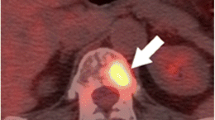

Prostate-Specific Membrane Antigen PET (PSMA PET)—a Technique for Detecting Very Early Recurrence

Although choline-based PET imaging is increasingly used for the detection of recurrent disease following curative therapy, several studies have reported concerns regarding sensitivity and specificity at low PSA levels [27–29]. Consequently, there is a need for a reliable diagnostic test in patients presenting with early biochemical failure. With this in mind, radionuclide imaging agents that target the cell surface receptor PSMA are receiving increasing attention [30••, 31, 32]. PSMA is expressed in the prostate, salivary glands, small intestine and kidneys. However, it is significantly overexpressed in prostate cancer cells when compared to the surrounding normal tissue [33, 34]. PSMA is a trans-membrane receptor that internalises bound ligands [35]. It is the internalisation of the ligand-radionuclide complex that is thought to account for the high-quality images produced by this technique [36].

Ga-68 PSMA-targeted diagnostic imaging has many advantages over traditional PSA testing, not least the ability to detect anatomically the location of lymph node metastases and distant soft tissue spread. Historically, salvage radiation therapy has been delivered to the prostatic bed without knowledge of the site of residual disease. This new modality opens the possibility of salvage surgical or radiation therapy that can be targeted to the correct location [37]. Two groups have published papers in 2015 examining the effectiveness of Ga-68 PSMA imaging for detecting recurrent prostate cancer [30••, 32]. Firstly, Ashfar-Oromich et al. performed a retrospective analysis in 319 patients who underwent Ga-68 PSMA imaging [30••]. In 292 of these patients, progressive disease was suspected following prior conventional treatment (e.g., radiation therapy/surgery). Ga-68 identified positive lesions in 50 % of men with a PSA <0.2 ng/ml, and as expected, the likelihood of a positive lesion correlated to PSA levels. From this cohort, tissue from 42 patients was isolated for further histological testing (biopsy/surgery) allowing comparison of images with gold standard histology. Lesion-based analysis from these 42 men gave sensitivity, specificity, negative predictive value and positive predictive values of 76, 100, 91 and 100 %, respectively. Secondly, Dietlein et al. have published a comparison of two PSMA-labelled radionuclides (Ga-68 and F-18). In 14 men with biochemical relapse, both PSMA-labelled isotopes identified positive lesions in 10 patients [32]. This study was limited by only two patients having histological confirmation of their positive lesions but did demonstrate the ability of this technology to highlight sites of residual disease or metastasis. Further studies are required with histological verification of positive lesions before it is adopted into standard practice.